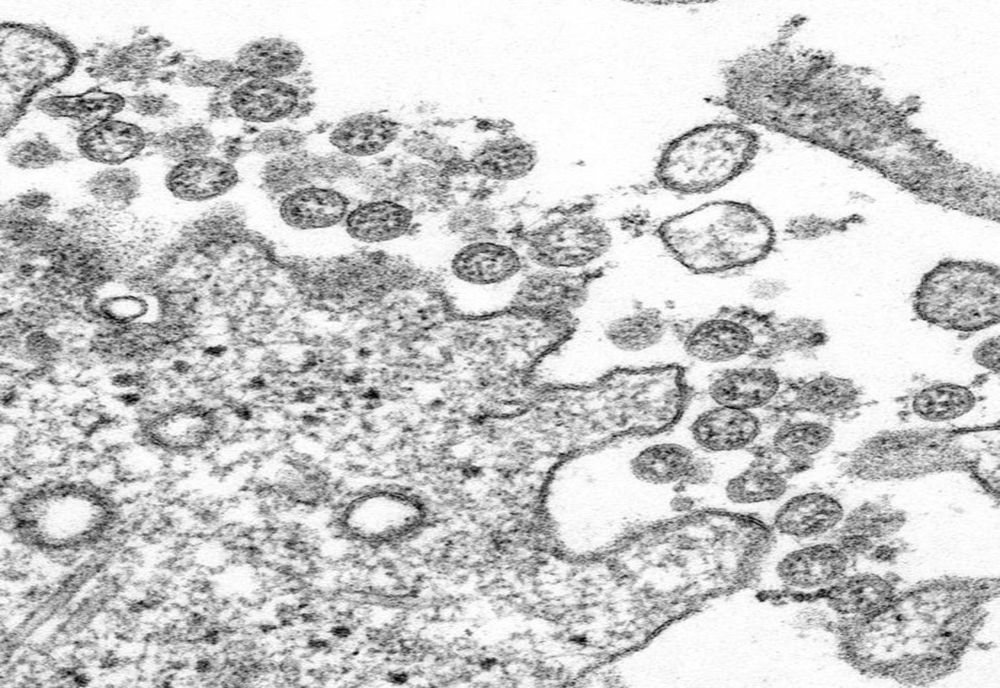

Virusologa Hyeryun Choe, principala autoare a studiului, a declarat că a putut determina în celulele de cultură că prin această mutaţie "virusul devine mult mai contagios". Această mutaţie denumită D614G sporeşte de între 4 şi 5 ori numărul, sau densitatea particulelor virale infecţioase (denumite virioni), care prezintă pe înveliş spicule glicoproteice proeminente, ce formează coroana virusului.

Aceste spicule glicoproteice, care dau aspectul de coroană sferică virusului, îl ajută să infecteze cu ajutorul receptorilor celulari ACE2.